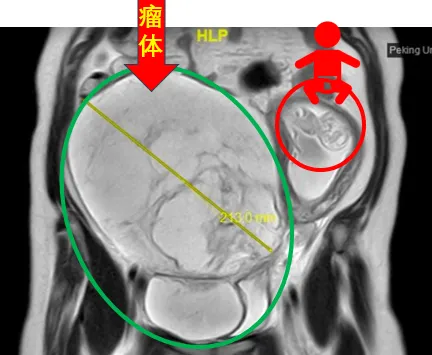

31岁的谢女士罹患静脉内平滑肌瘤病两年多,正鼓起勇气准备接受治疗时,意外发现自己怀孕了。在孕期激素的“加持”下,谢女士盆腔内的瘤体迅速增大至足月胎儿大小,血管内瘤栓沿着右侧髂静脉、下腔静脉一直“爬”到右心房,甚至在心脏舒张期进入右心室,使她处于随时可能猝死的高危风险下。

▲2024年4月,谢女士的核磁共振图像显示,巨大肿瘤将她的子宫挤到了腹腔左侧